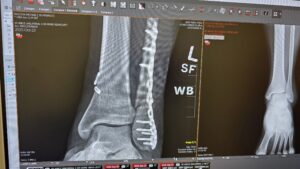

On the second day riding, I had a silly accident. I was riding around a berm and took the turn wrong, losing control. I flipped over the front of the bike while my left ankle was pinned under the bike. This twisted my ankle 180 degrees, snapping the tibula, fibula and tearing a ligament. The adrenaline kicked in immediately, and the pain was not too intense at first. I stood up and raised my arm to make sure any oncoming riders would see me. There was a group of riders nearby that were kind enough to ride my bike back to the parking lot. They had a side-by-side they let me sit in and gave me a ride back to the staging area. By the time all linked at the parking lot and loaded the bike, my ankle had inflated to the size of a softball. Signs of bruising had already begun and the pain was increasing every minute. Dave set the GPS to the nearest hospital and they took care of me.

The hospital in Eagle Mountain, Intermountain Health, was very impressive with their speedy patient processing time. I filled out a few papers and within ten minutes I was in a room prepping for xrays.

The surgery went well and as expected. Dr. Joos in Provo, Utah did a fantastic job installing my new ankle hardware. It required 8 screws to hold the titanium plate to my ankle, and two anchors to hold together the ligament. Fortunately for me I was able to receive a nerve blocker injection prior to the surgery. I had my tonsils removed in 2016 and forgot that was a surgery. With the anesthesia I don't remember anything, and it was over in the blink of an eye. The nerve block helped with the pain afterwards and my leg was entirely numb for about two week later. The pain really set in once the nerve blocker subsided, which happened rapidly after that two week mark.